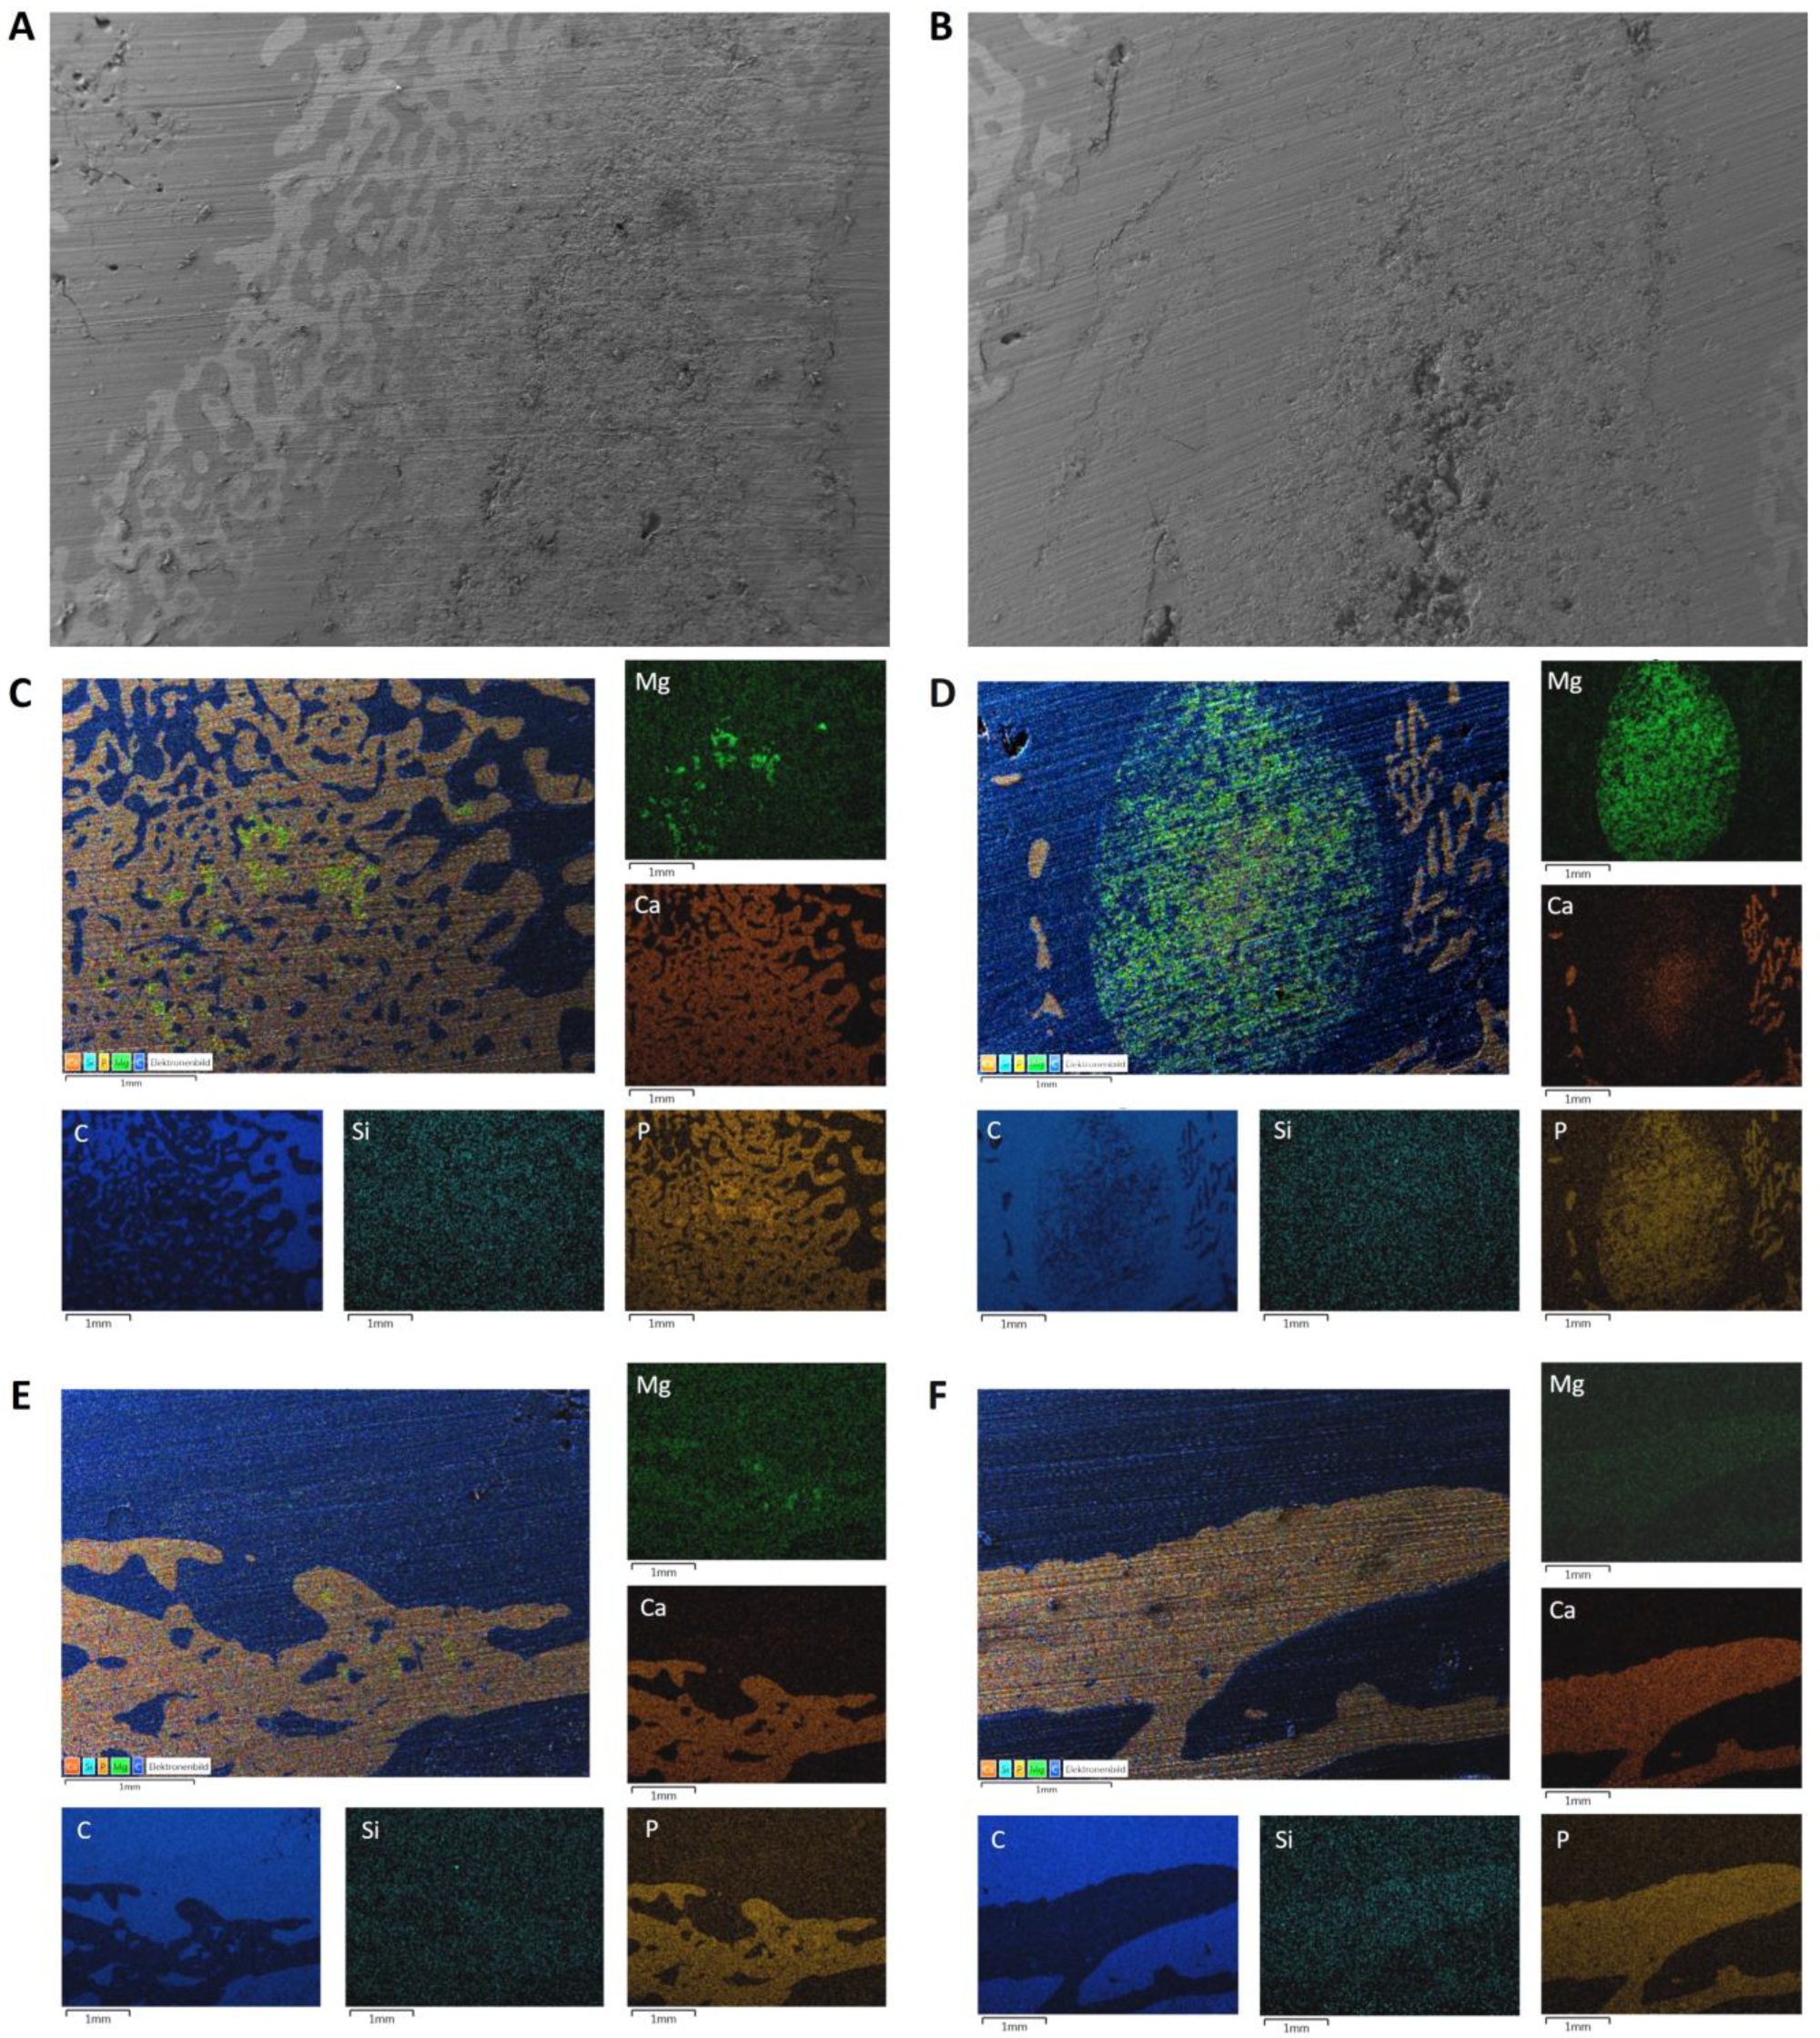

3.2. SEM/EDX Analyses before Implantation

3.7. SEM/EDX Analyses after Implantation